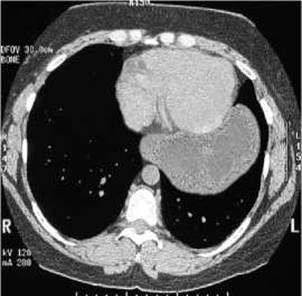

Мал. 130. Параезофагальна грижа на комп’ютерній томограмі.

Грижі стравохідного розтвору діафрагми являють собою потрапляння через розширений стравохідний розтвір у заднє Середостіння кардіального відділу шлунка. Такі грижі можуть бути фіксованими і нефіксованими (ковзними). Серед ковзних гриж розрізнюють аксіальні та параезофагальні (мал. 128). За наявності аксіальної грижі кардіальна частина шлунка періодично або постійно зміщується у грудну порожнину, стравохід повністю знаходиться у грудній порожнині (мал. 129). При параезофагіальній грижі у грудну порожнину проникає склепіння шлунка (мал. 130), іноді сальник, причому кардіальна частина шлунка і черевна частина стравоходу залишаються під діафрагмою. Грижі легко вправляються, але можуть ущемлюватись. Хворі скаржаться на печію, відригування, біль за грудиною. Рентгенологічно на тлі тіні серця виявляють просвітлення газового пухиря шлунка, інколи з горизонтальним рівнем рідини. Для виявлення грижі стравохідного розтвору діафрагми застосовують контрастування стравоходу і шлунка барієвою сумішшю, хворого просять прийняти горизонтальне положення і напружити м’язи черевного преса.